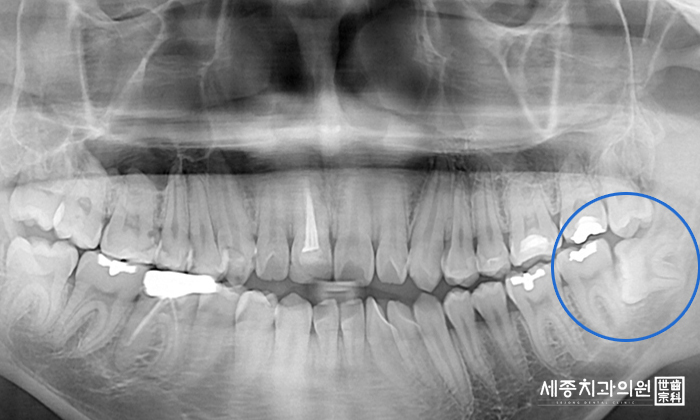

올바르게 자리를 잡아 어금니의 기능을 해내는 사랑니라면

발치를 하지 않아도 되지만, 대부분의 사랑니는 옆으로 기울어져 나거나

잇몸을 다 뚫지 못한채로 매복되어 인접치아에 영향을 주게 됩니다.

3. 정확한 진단을 위한 3차원 C.T. 촬영

3차원 C.T.촬영으로 사랑니의 뿌리와 신경관의 위치 등을

정밀하게 진단합니다.